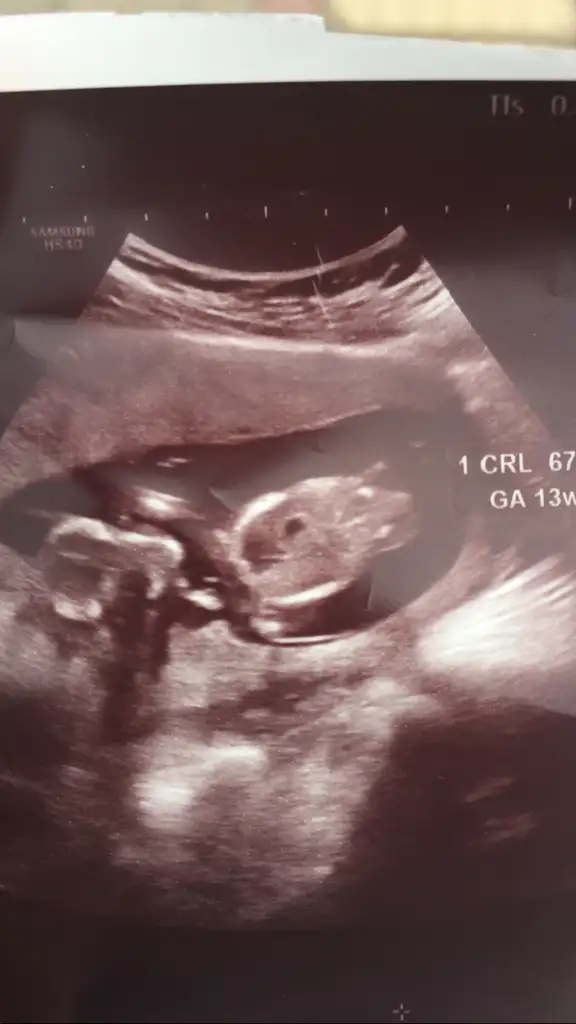

dr soylemeden siz gorun genital nub teorisi ( bebegin cinsiyeti)

tahmin alabilir miyim

Merhaba 12+1 günlüğüz doktor emin olamadı ama erkek demiştiniz 11 haftalıkken şimdi ne görünüyo acaba bacak arasında bişeyler var gibi 😌